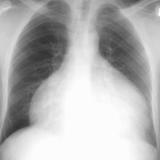

Heart failure

Album: Heart failure

Date: 11/05/2005

Size: 24 items

Views: 57365